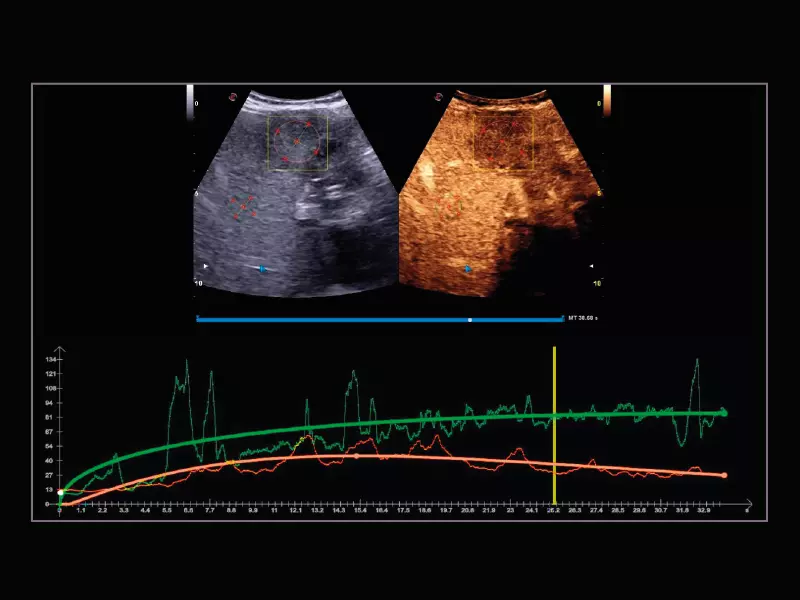

MyLab™9 Platform - QPack CnTI™ perfusion analysis post RF ablation

MyLab™9 Platform - QPack CnTI™ perfusion analysis post RF ablation